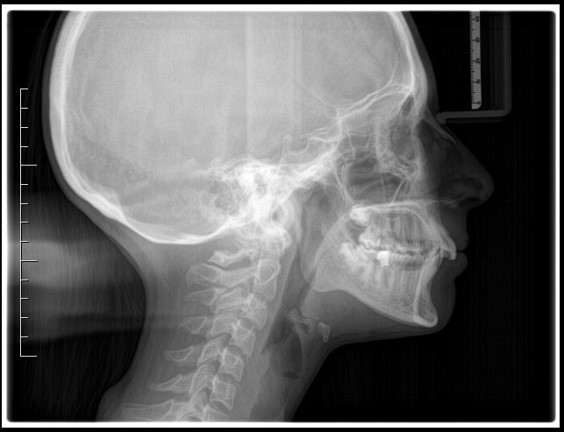

Teleradiografia latero-laterale pre-trattamento

Fig. 2 Teleradiografia latero-laterale pre-trattamento